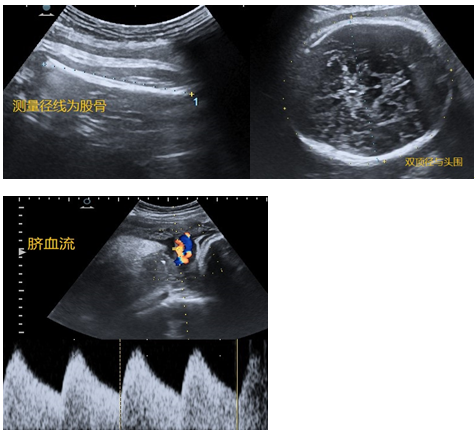

孕28-34周:TA继续生长发育,变得强壮有力。孕32周之后的TA 已经没有足够的空间畅游了,四肢也蜷曲起来,动作幅度也变小,胎位较为固定,也导致超声检查变得困难。尽管如此,我们依然通过超声关注两个方面(图7 ):一,TA的大小合适吗?晚孕期的TA逐渐展示出个体差异性,变得不那么“标准”,如有的腿短一些,有的头大一点,有的又太胖了。我们在超声下测评TA的各项数据是否符合标准孕周,如果实际孕周与标准孕周相差在两周以内也是允许的。二,TA赖以生存的附属三件套(胎盘脐带羊水)是否正常?胎盘是否成熟或老化?脐带血流是否正常?羊水量多还是少?当然除了超声,临床医生也会结合其他检查综合评估胎儿在母体的情况。

图7 超声显示晚孕

孕37-40周:TA已足月。超声下判断TA的胎位可谓轻而易举,瞬间确定。TA的各种系统器官已经发育成熟,头身长大缓慢、主打“养膘”。我们在超声下测量TA的双顶径、头围、股骨、腹围等各项参数,用以估算出TA的体重。我们通过超声观察TA的附属三件套的变化。羊水量逐渐变少。缺乏了羊水的映衬,超声对TA的显示愈发困难和模糊了(图8:超声显示晚孕足月)。

图8 超声显示:晚孕足月